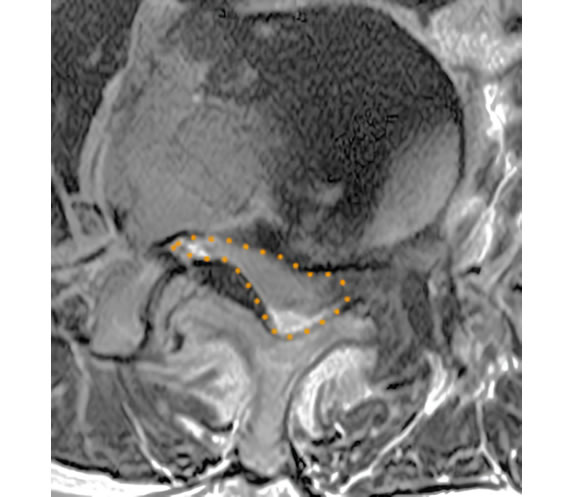

腰椎椎間板ヘルニア摘出前前

摘出後